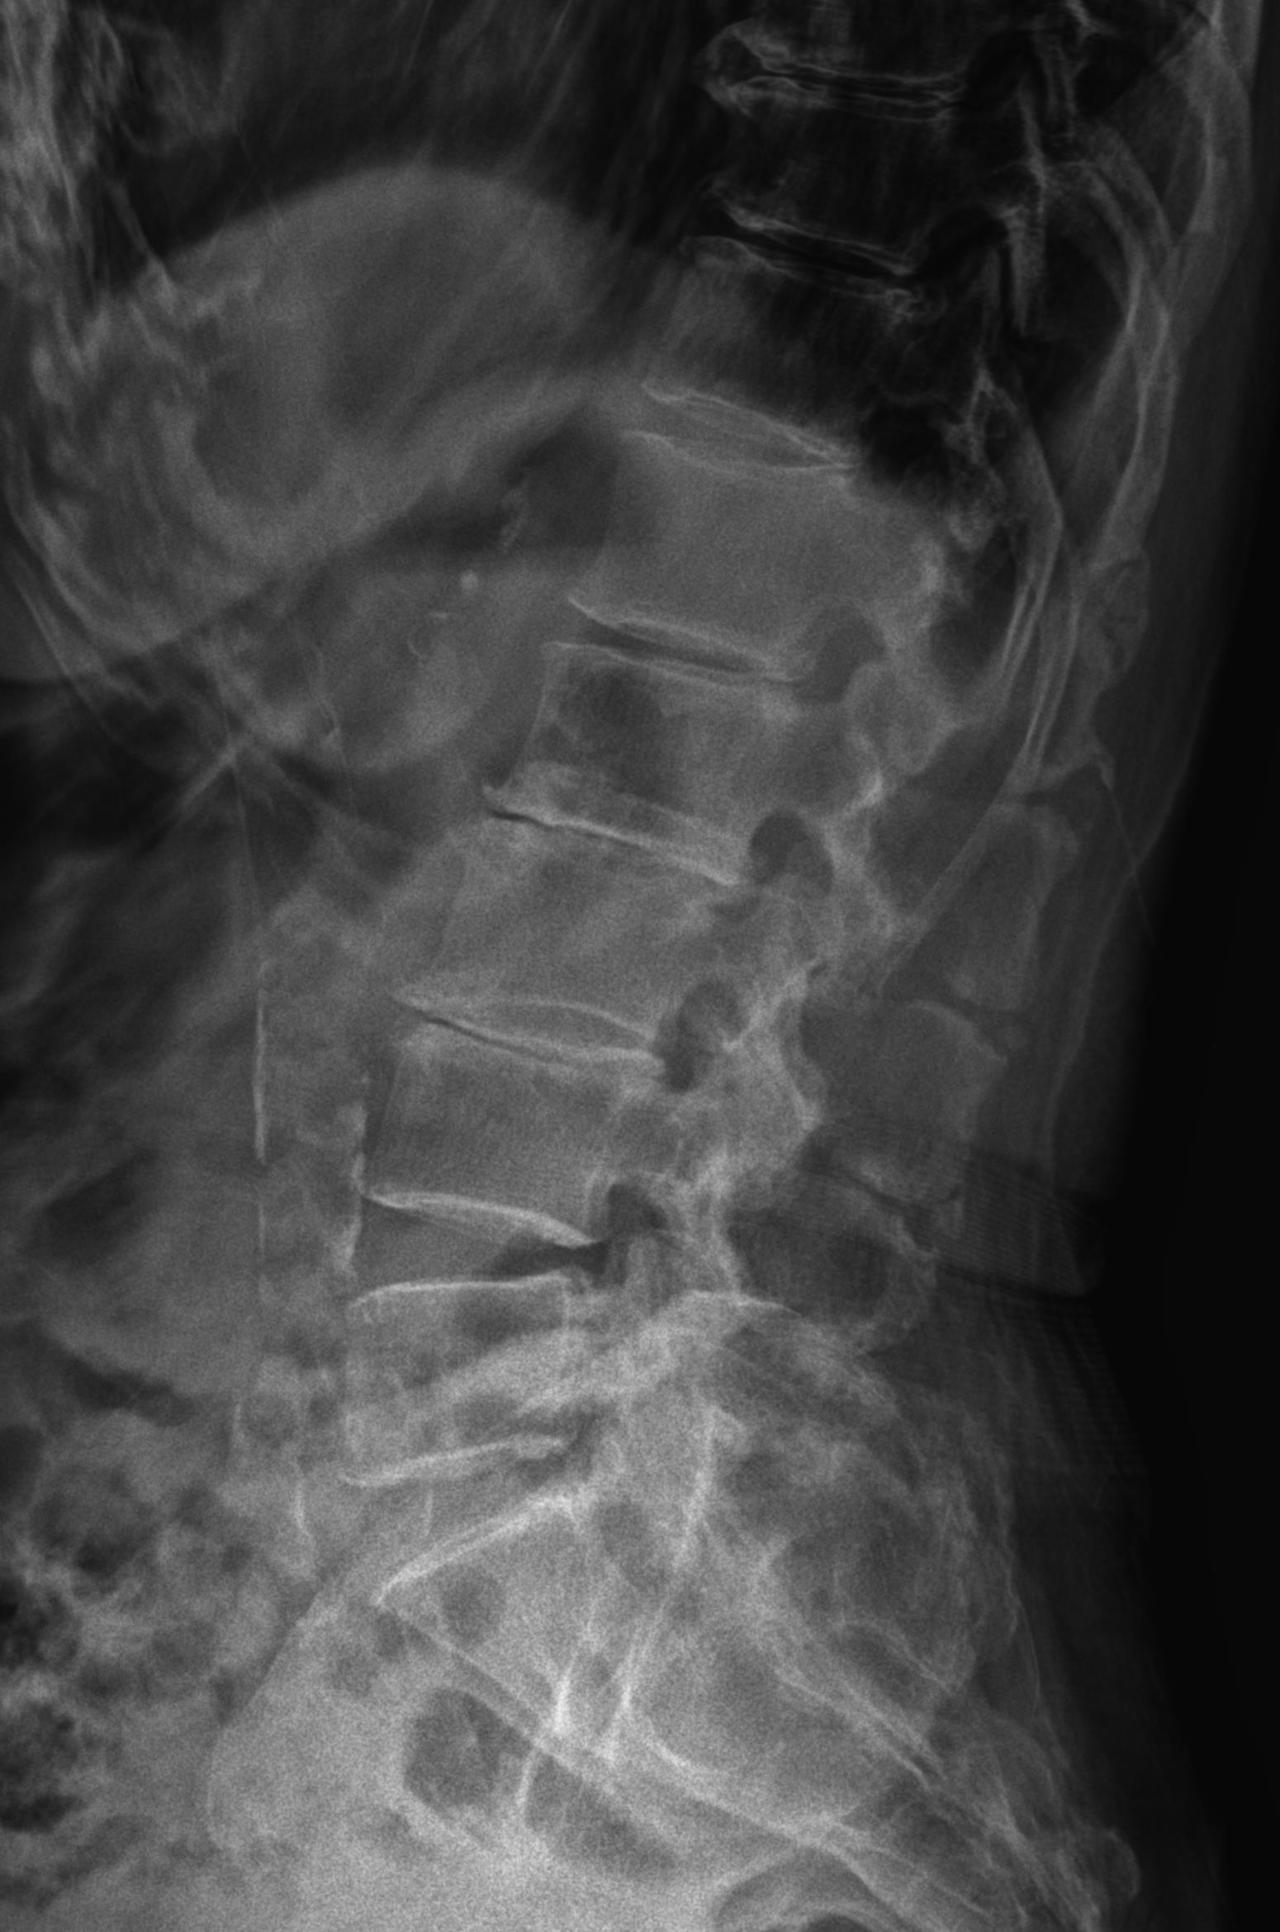

척추 협착의 정확한 명칭은 척추관 협착증입니다. 이것은 디스크 탈출을 포함하는 좀 더 커다란 의미의 질병입니다. 먼저 많은 사람들이 착각하는 포인트를 짚고 넘어가면 우리가 흔히 말하는 척추 X-ray의 측면 사진에서 척추뼈 사이가 좁아진 것은 척추관 협착이 아닙니다.

20221122155050_vU9.jpg 체크> 요추 2,3,4번 사이에 좁아진 간격을 두고 척추관 협착증이라고 하지는 않는다.

척추관 협착이라는 것은 측면 사진이 아닌 척추를 횡단면으로 잘랐을 때 보이는 척수가 지나가는 통로(척추관)가 좁아진 것을 척추관 협착증이라고 이야기합니다.